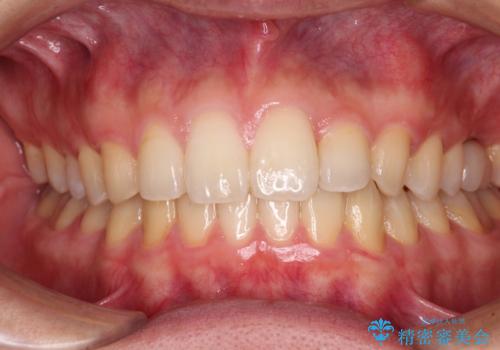

下の前歯が上の前歯を突き上げるように咬合するため、咬み合わせの位置を改善しながら隙間を閉じていきました。

元々の歯並びが悪くなかったため、9ヶ月で綺麗に仕上がりました。

すきっ歯は後戻りを起こしやすいため、上下ともに歯の裏側を細いワイヤーで固定した上で、リテーナーのマウスピースを装着していただいています。